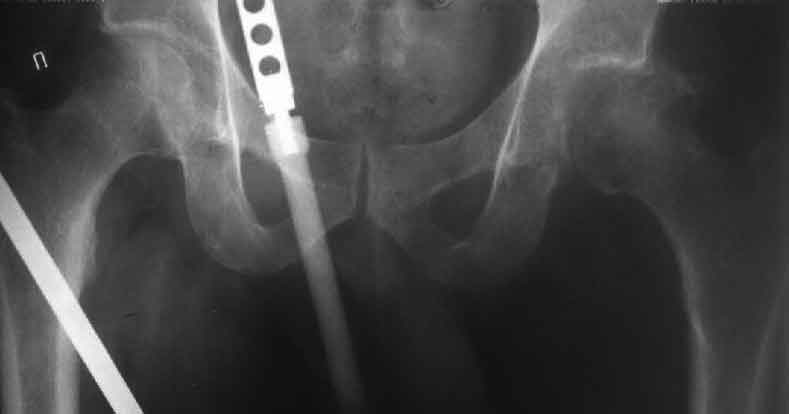

Еще пара фото, ситуация несколько иная, задачи те же, открытое вправление застарелого вывиха в 2002, молодой возраст. Сейчас госпитализирована для эндопротезирования.